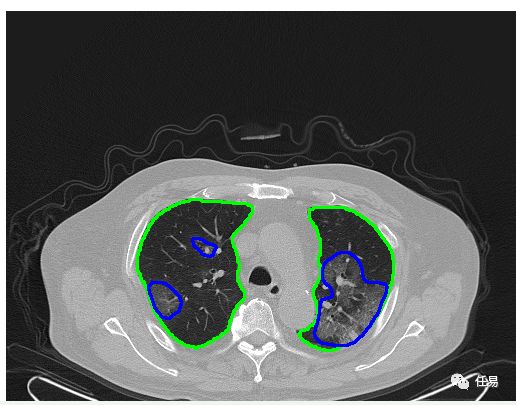

2020年跟古代的最大不同,是我们多了人工智能AI技术。AI识别CT的原理,其实就是把图片进行切割,然后进行卷积,识别边缘,包括识别颜色,就是我们熟知的大白肺,所以只要有了足够的、经过标注的图像数据,我们就能用AI识别出来。

2月21日,腾讯人工智能CT设备在武汉多家方舱医院部署,用腾讯觅影AI辅助诊断CT片子,可以在十秒完成AI评定,一分钟内给医生提供辅助诊断参考。同日,阿里达摩院发布了AI诊断,在湖北、上海、广东、江苏等16个省市部署了26家医院,并对3万个临床疑似新冠肺炎病例CT影像进行了诊断,准确率达到96%,但是需要20-30秒评定,我大鹅厂略胜一筹。

单纯人工智能还不足以取代资深医生,但是当医生的助理,识别有风险的病人,已经完全足够了。目前治疗期患者每5天要做一次CT检查,一台CT机器每天可以拍300人次CT,每天如果可以用AI辅助处理15000张CT,那么将极大程度的节省医务人员的体力精力(一个人的片子要看5-10分钟)

AI识别CT的原理,其实就是把图片进行切割,然后进行卷积,识别边缘,包括识别颜色,就是我们熟知的大白肺,所以只要有了足够的、经过标注的图像数据,我们就能用AI识别出来。